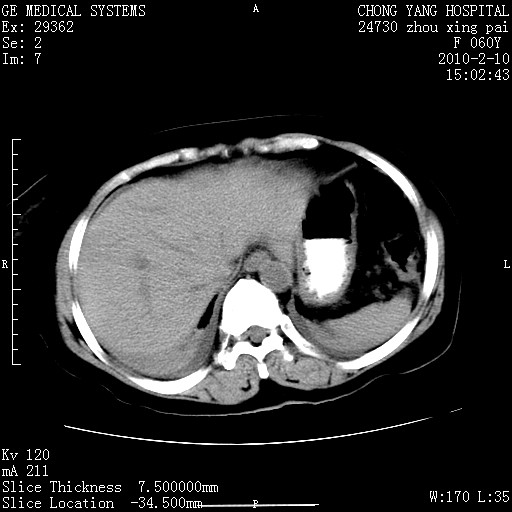

标题: CT24682:F60Y 腹痛 其它不详 [打印本页]

标题: CT24682:F60Y 腹痛 其它不详

胆总管末端梗阻!结石?肿瘤?建议增强!必要时行ercp!

胆总管末端梗阻!结石?胰腺影增粗,以胰腺头部为著,胰周看见渗出影,双侧胸腔积液,(胸膜反应)考虑胰腺炎。

1)胆总管末端梗阻,不排除结石所致可能。2)胰腺炎。3)慢性胆囊炎可能。4)左侧输尿管上段扩张。5)少量腹水。6)双侧少量胸腔积液,伴两下肺部分肺萎陷。

1)胆囊炎。2)胆源性胰腺炎。3)右肾周筋膜增厚,肾旁前间隙积液。4)左侧输尿管上段扩张。5)少量腹水。6)双侧少量胸腔积液,伴两下肺部分肺膨胀不全。

急性胰腺炎所致胆总管扩张!